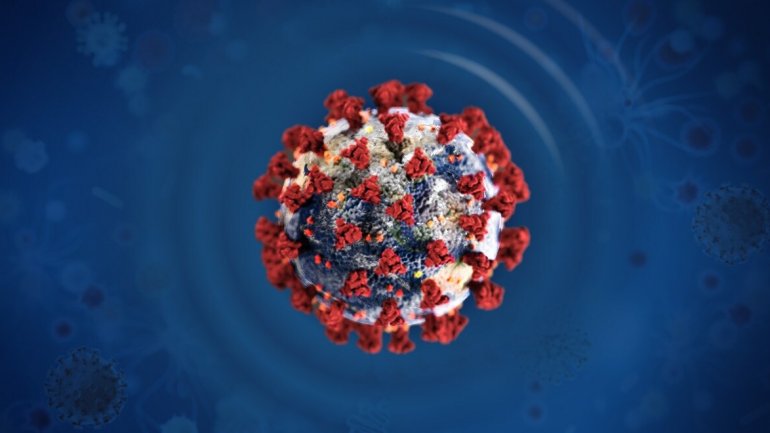

Ο αποτελεσματικός αερισμός είναι βασικός παράγοντας για την αποτροπή της εξάπλωσης του κορωνοϊού

Δεδομένου ότι ο SARS-CoV-1 που ξέσπασε στο Χονγκ Κονγκ πριν από περίπου 17 χρόνια έχει...